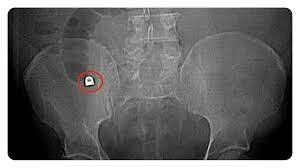

1896 se comienzan a realizar procedimientos radiológicos para la extirpación de cuerpos extraños de forma segura y precisa.